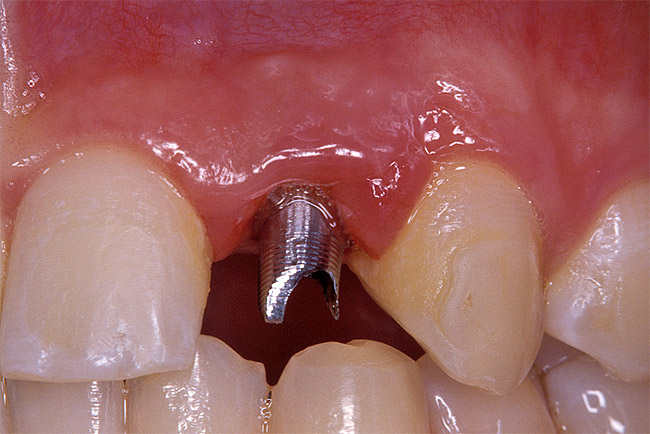

Before the day of surgery, the patient was seen by the orthodontist for the removal of the orthodontic brackets. The patient still was not pleased with the position of the two centrals, and it was determined that this would be addressed after implant placement (Figure 13A). The anatomical variations of the crestal tissue and lack of interdental papilla can be appreciated in the close-up views of the right and left sites (Figure 13B and 13C). There were no surprises on the day of surgery as all of the decisions were made during the planning phase, before the scalpel ever touched the patient. The occlusal view of the CT 3D model revealed the wider alveolar ridge on the right side and thinner crest on the left side (Figure 14A). This was confirmed when the full thickness mucoperiosteal flaps were elevated, and the underyling bone revealed (Figure 14B). The tooth-borne templates were designed to facilitate the drills and drilling sequence specific to the diameters of the predetermined implants (Figure 15A). Each template contained an embedded 5-mm long stainless steel tube, which was approximately 0.2-mm wider than each drill (just wide enough to allow for the drills to rotate freely). Once positioned over the natural teeth, the template was secure and offered precision accuracy in transferring the implant locations from the original software-designed plan, allowing the potential for internal and external irrigation (Figure 15B). The 3.7-mm diameter Tapered Screw-Vent implant drilling sequence requires three drills: pilot, intermediate, and final sizing. Thus, three separate templates were fabricated to a.commodate these sizes. The templates were removed easily and replaced with the next sequential size in less time than it takes to change the drill on the surgical handpiece. After the osteotomies had been.completed, the implants were delivered to the site (Figure 16A and Figure 16B). For this internal hex connection implant, the author r.commends that the flat of the antirotational hex be positioned to the facial for proper orientation of the restorative.components (Figure 17A). Preprepared margins were created from a milled titanium fixture mount transfer post, which was delivered to the implant as support for an immediate transitional restoration. The facial “dot” helped confirm the orientation of the abutment to the facially positioned flat side of the internal hex connection (Figure 17B). Before cementation of the transitional acrylic restorations, a closed-tray, fixture-level impression was made, and a soft-tissue model fabricated.

Figure 16a  After (A) the osteotomies were completed, (B) the implants were placed.

Figure 16a

Figure 16b  After (A) the osteotomies were completed, (B) the implants were placed.

Figure 16b